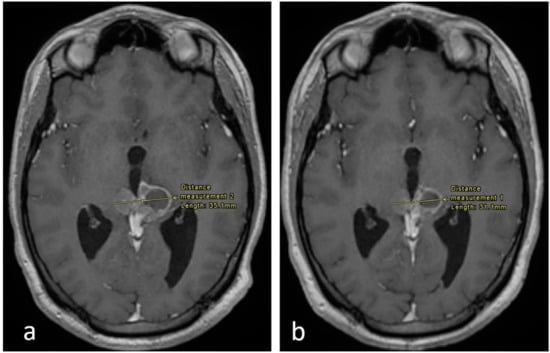

In July 2018, follow-up MRI showed regression in the size of the pineal tumor. To further maximize response, and in-line with the multidisciplinary decision, the patient then received radiotherapy for 2 months, after which MRI showed further regression, followed by stability in size noted in September 2019.

Figure 2. Axial enhanced T1 weighted images of the brain at the level of the pineal region. (a) Imaging performed in September 2017 and (b) in December 2017. There is an interval decrease in the size of the tumor, as shown.